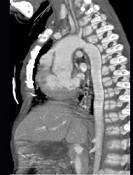

问题 患者,男性,8岁,发绀、气促,易感冒,彩超提示只见一个心室,CT检查如图所示,请选择正确的选项 ( )

选项 A、考虑三尖瓣狭窄 B、右前斜位示左心房增大,心后上缘后突压迫冲钡食管 C、左前斜位示心影向后下方突出 D、考虑二尖瓣狭窄

答案 BCD